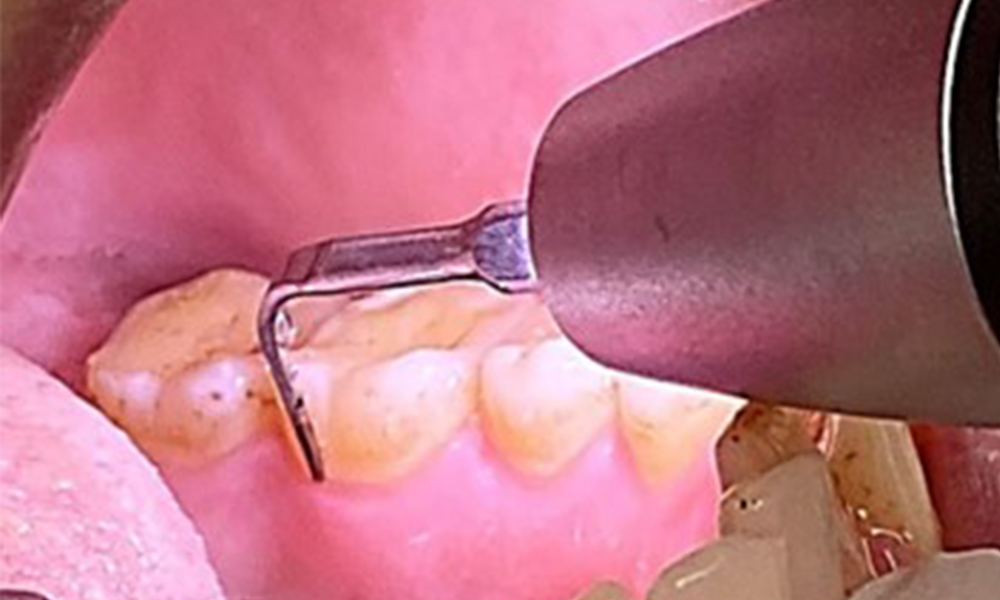

Поради иначе благоприятното общо медицинско състояние, нуждите, определени по време на оралния преглед, ще бъдат решаващи за лечението. От съществено значение ще бъде периодичното определяне на дълбочината на сондиране. Гингивалното кървене намалява при пушачите, поради което клиничната диагноза на пародонтита може да се постави само чрез сондиране (фиг. 7). Поставянето на изключителен акцент върху определянето на индексите на кървене може да замъгли съществуващ пародонтит или гингивит. (5)

- Важно е да се документират резултатите от контролния преглед. По време на всяка среща трябва да се определя статусът на кървене при сондиране (BOP) за измерване на дълбочината на пародонталния джоб в ранните етапи на заболяването. Това е особено важно при пушачите поради намален приток на кръв към тъканите.